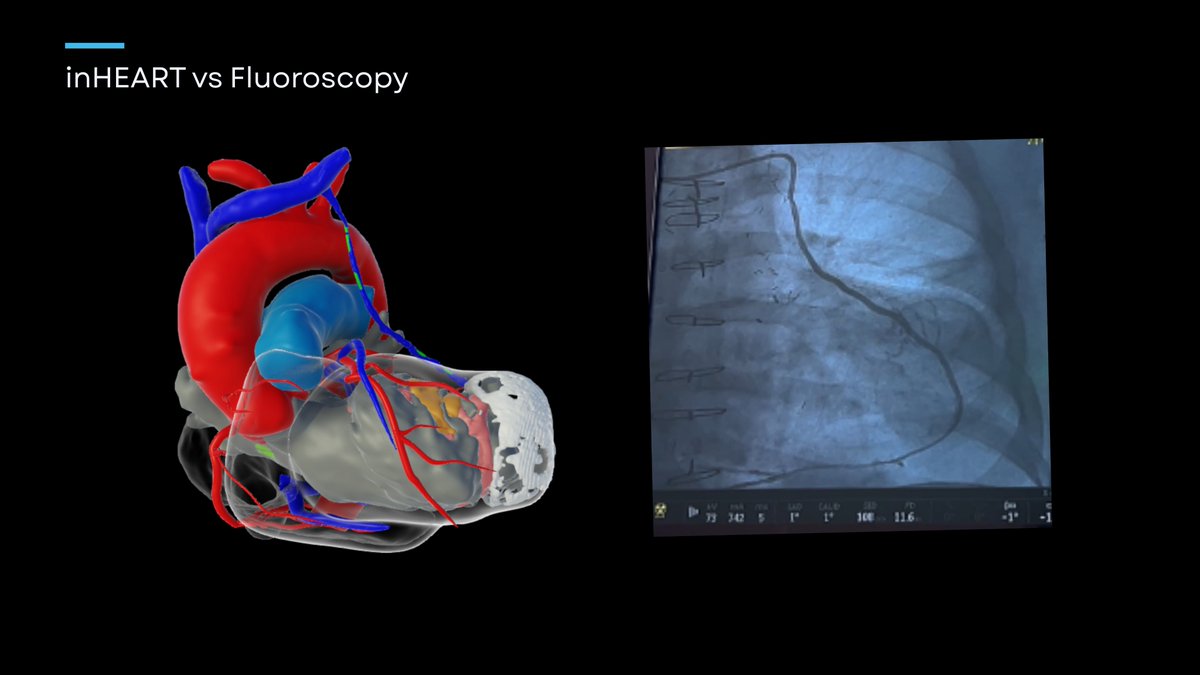

Thinking of transforming your approach to #PVC procedures? Join us on December 5 for an exclusive inHEART #webinar: "Advanced Cardiac Modeling to Guide Complex PVC Procedures" led by experienced henry zhou physician users. Whether you're a specialist in electrophysiology or a

Thinking of transforming your approach to #PVC procedures? Join us on December 5 for an exclusive inHEART #webinar: "Advanced Cardiac Modeling to Guide Complex PVC Procedures" led by experienced <a href="/inHEART/">henry zhou</a> physician users. Whether you're a specialist in electrophysiology or a